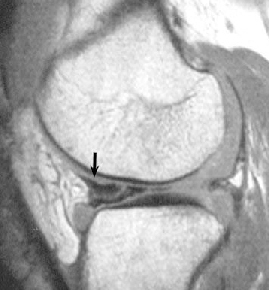

• ACL 손상 방사선 사진3